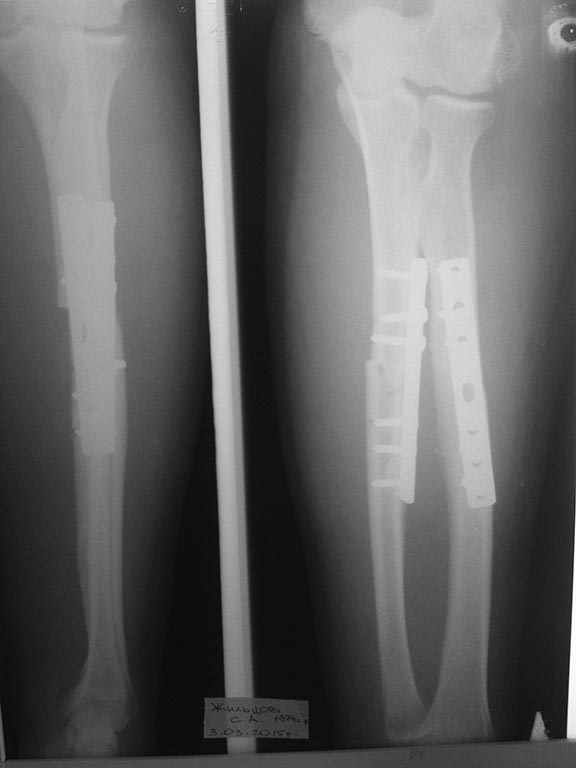

Пациент 1974 г.р., получил травму в конце января 2015 года- закрытый

перелом обеих костей левого предплечья в результате падения на руку

тяжелого предмета- ствола дерева (снимок 1). 03.02.15 оперирован-